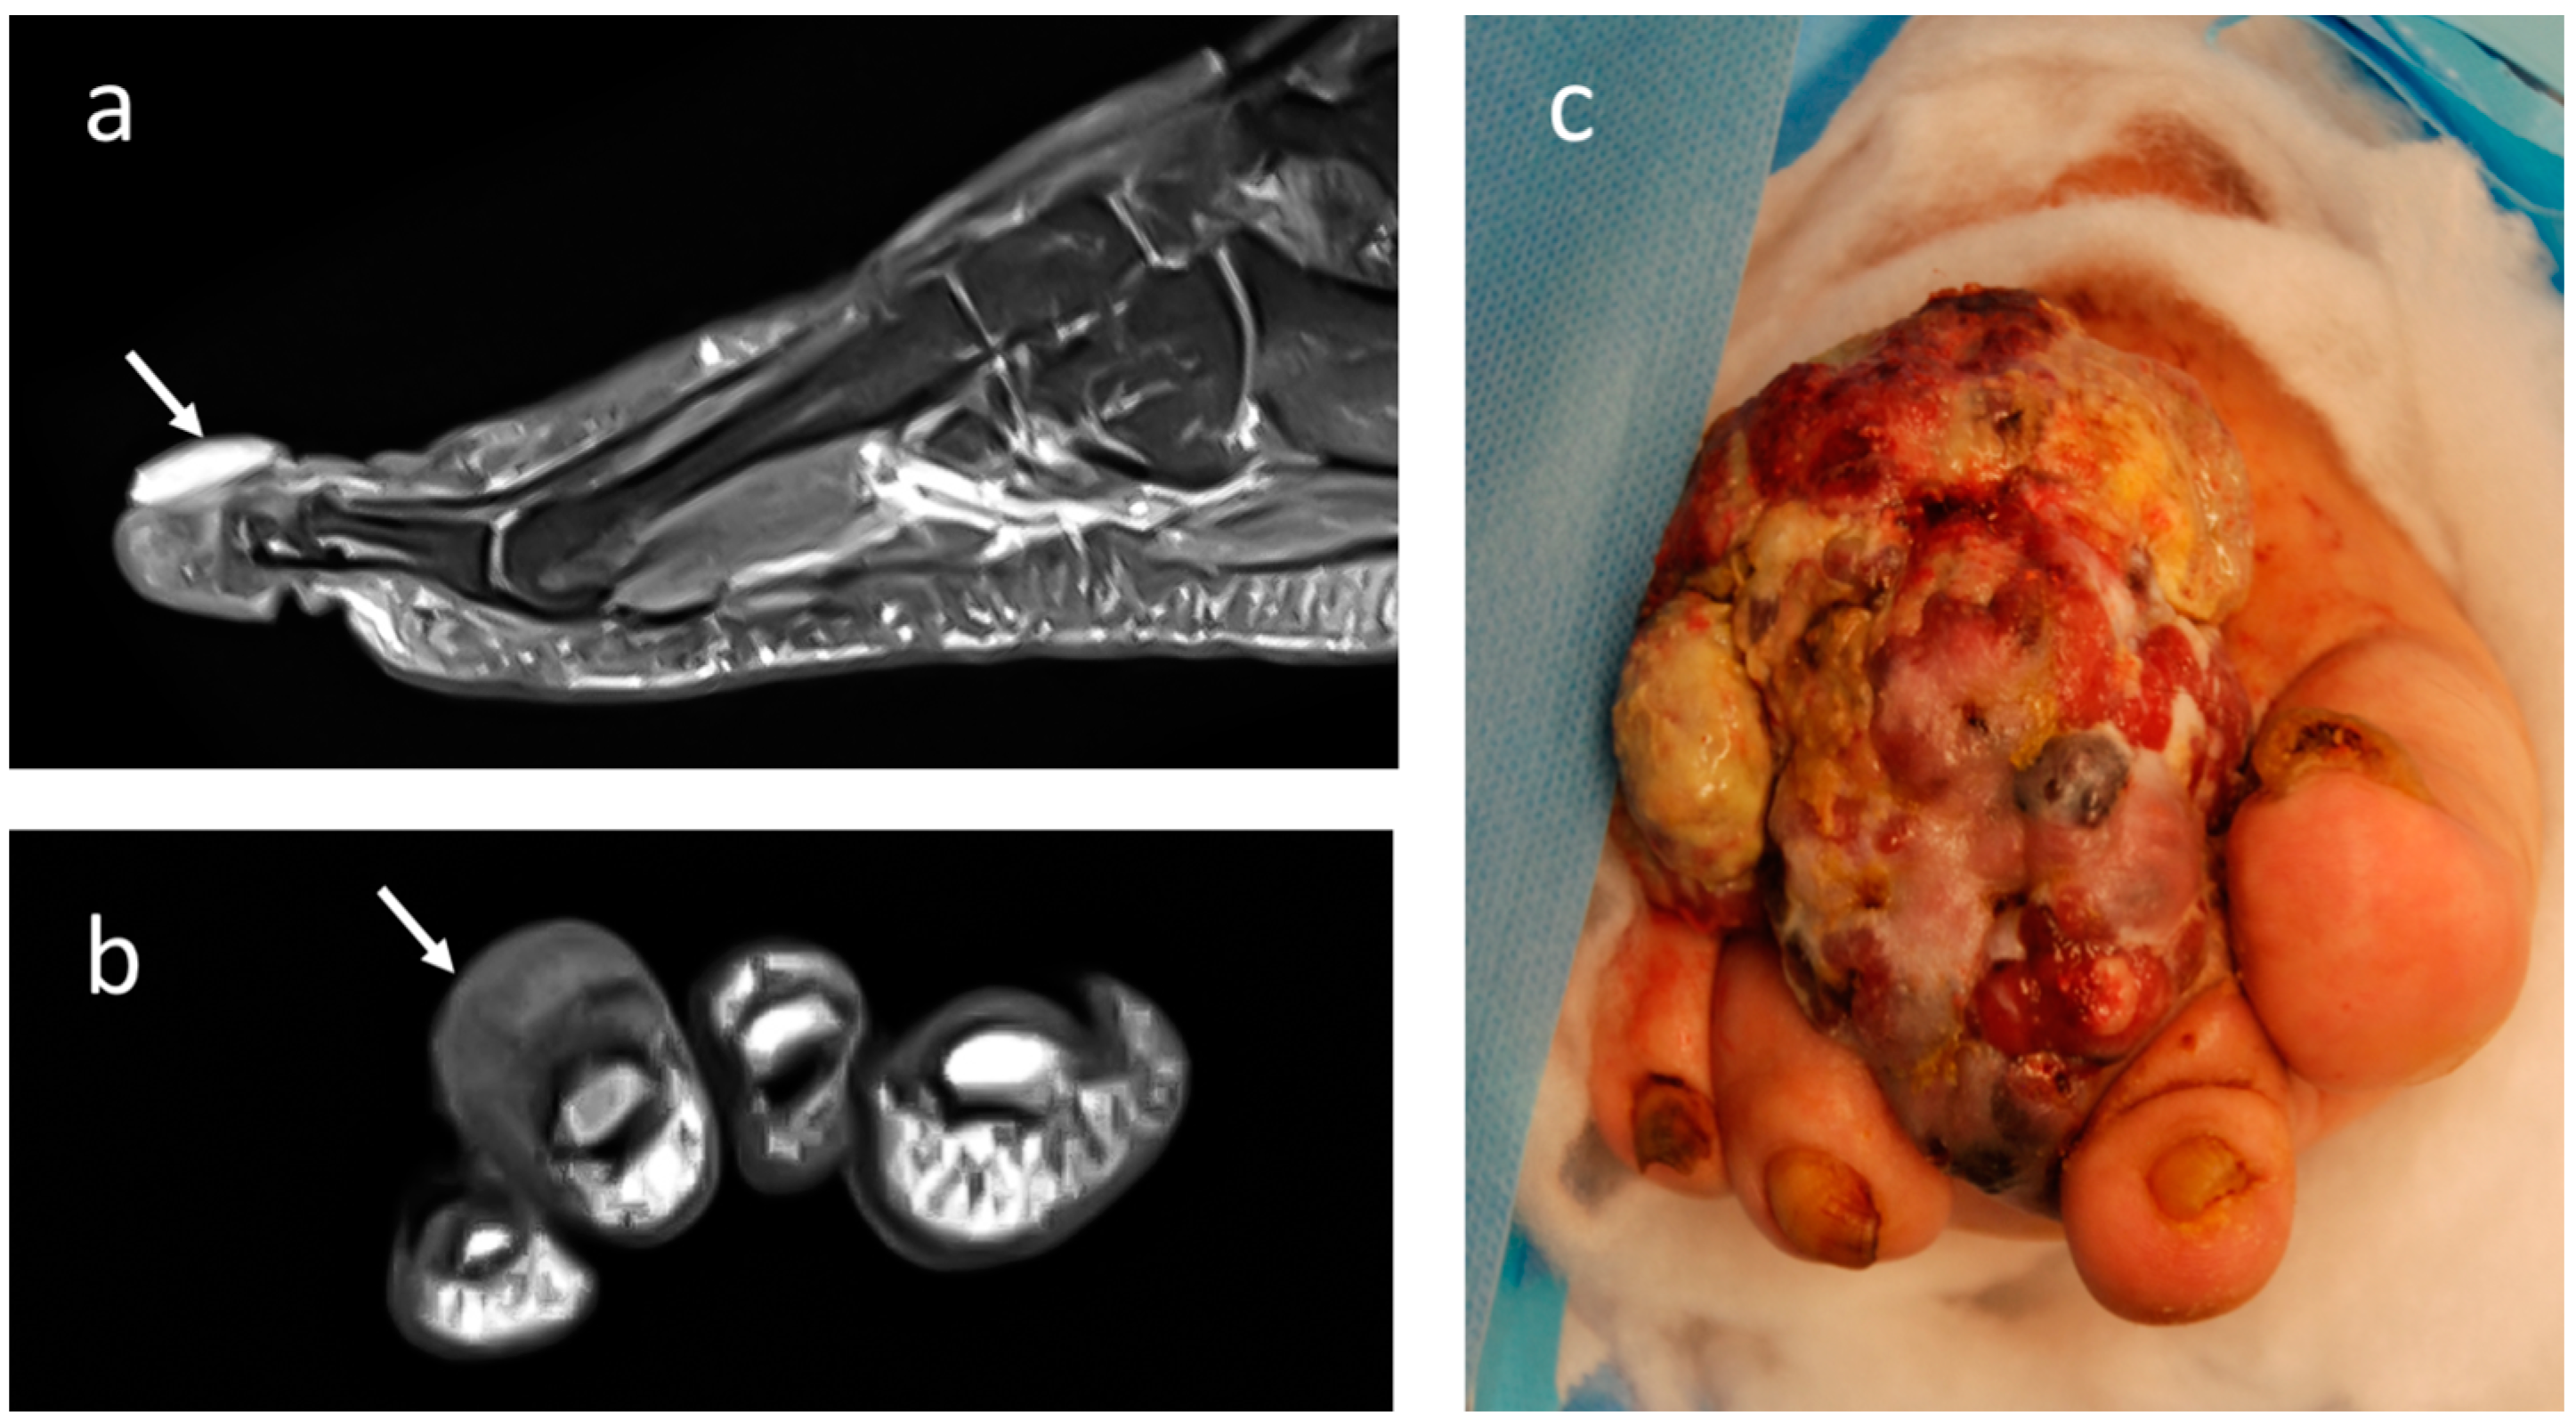

4.3. Synovial Sarcoma